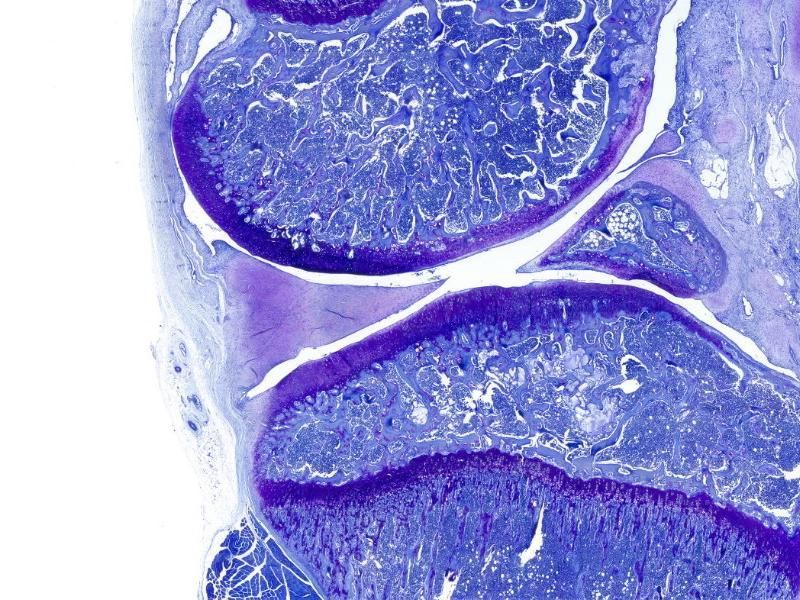

甲苯胺蓝染色

编号:YSY10118

番红-固绿染色(软骨)

编号:YSY10119